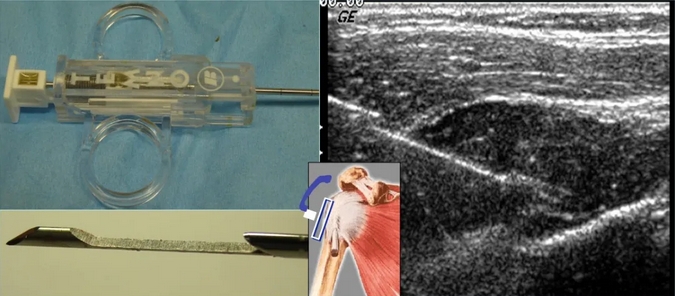

3.5 介入性超声是“魔法棒”

接下来,让我们重点关注肌骨介入性超声的奇妙世界。

肌骨介入超声,这项技术就像是医生手中的魔法棒,它利用高频超声波,穿透皮肤和组织,既是一种诊断工具,更是一种治疗的精准导航。它以其精准、微创、安全的特点,为肌骨疾病的治疗带来了革命性的变革,不仅提高了治疗的成功率,减少了患者的痛苦,还为患者的快速康复提供了可能。

超声介入治疗操作技术

想象一下,一位患者因为长期劳作,手腕出现了麻木和疼痛,这可能是腕管综合征在作祟。通过肌骨介入超声,医生可以清晰地看到神经受压情况,并在超声的实时监测下,将一针药物精确地注入到受压的神经周围,缓解症状。这就是肌骨介入超声的魅力,它能够以最小的创伤,达到立竿见影的治疗效果。这项技术的应用非常广泛,除了可以用于治疗腕管综合征,还可以用于肩周炎、网球肘、高尔夫球肘等常见的肌骨疾病,及关节腔注射、囊肿穿刺、甚至是肌腱病变的介入治疗。在这些操作中,肌骨介入超声都能提供精准的定位,确保治疗的安全性和有效性。

超声引导骨肉瘤介入诊疗

而且,肌骨介入超声还有一个巨大的优势,那就是它的实时性和动态性。在治疗过程中,超声医生可以实时观察到治疗区域的变化,临床医生参与其中,可以根据需要调整治疗方案,确保治疗的精确性。这种动态的观察和调整,是传统静态影像技术无法比拟的。在我院多年超声科日常工作中,肌骨介入超声与临床专家通力配合,已为患者提供个性化的治疗方案,解决病痛,深受临床医生的肯定和患者的好评。